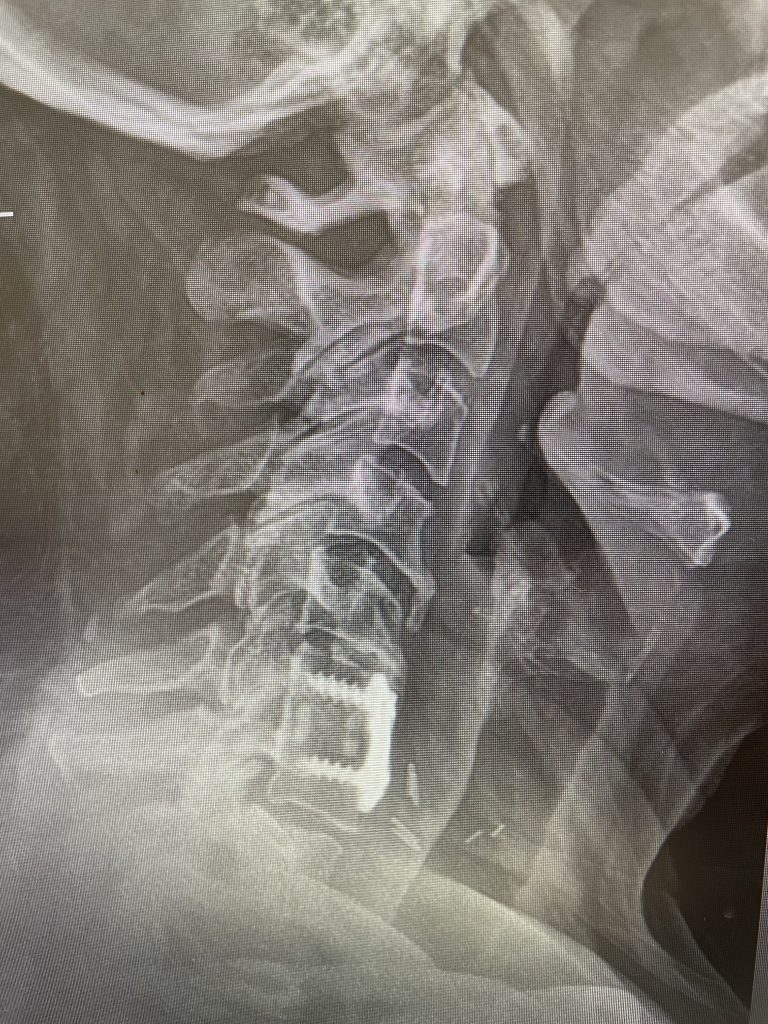

Patients may require an occipital-cervical fusion for both cranio-cervical and atlanto-axial instability, depending on the anatomy. Patients who have long segment posterior cervical fusions can sometimes […]